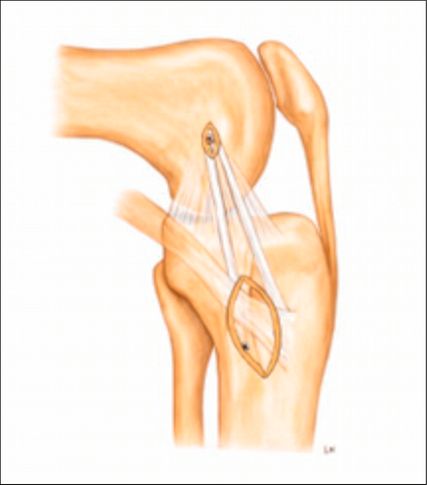

Kombinierte Verletzungen des medialen Kollateral- (MCL) und des vorderen Kreuzbandes (VKB) zählen zu den häufigsten multiligamentären Knieverletzungen. Bei vermeintlich isolierten VKB-Rupturen werden MCL-Verletzungen häufig unterschätzt bzw. nicht diagnostiziert. Dadurch kommt es nach VKB-Rekonstruktion und medialer Instabilität zu vermehrten VKB-Rerupturen. Eine optimale Therapie der anteromedialen Rotationsinstabilität (AMRI) erfordert daher eine detaillierte Diagnostik.

Isolierte oder kombinierte Verletzungen des medialen Kollateralbandes sind häufig. Zunehmende Evidenz zeigt, dass eine residuelle MCL-Laxität zu nachfolgenden Meniskus- und Knorpelschäden sowie zu einer erhöhten Belastung des VKB bzw. der VKB-Plastik führen kann, was wiederum das Risiko für eine VKB-Reruptur erhöht. Die aktuellen Therapiestrategien der AMRI variieren und umfassen sowohl operative als auch konservative Behandlungsansätze. Ein Konsens hinsichtlich Diagnostik, Klassifikation und Therapie der AMRI fehlt bislang aufgrund der begrenzten klinischen Studienlage.